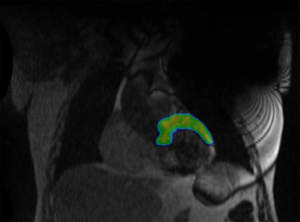

Neue Therapie für Patienten mit lebensbedrohlichen Herzrhythmusstörungen10. Mai 2019 Unter MRI Bildgebung wurde der betroffene Anteil des Herzmuskels gezielt bestrahlt (in Farbe). Bild: © Universitätsspital Zürich Weltweit erstmals ist es am Universitätsspital Zürich (USZ) gelungen, einen Patienten mit lebensbedrohlichen Herzrhythmusstörungen mit einer MR-geführten Radioablation erfolgreich zu behandeln. Seit April 2019 können in der Klinik für Radio-Onkologie am USZ Patientinnen und Patienten an einem MRI-Linac-Gerät behandelt werden. «Mit diesem Linearbeschleuniger können wir vor und während der Bestrahlung durch MR-Bildgebung jedes Ziel im Körper eines Patienten verfolgen und die Bestrahlung in Echtzeit steuern und anpassen», erklärt Dr. Tanadini-Lang, Leitende Physikerin der Klinik für Radio-Onkologie. Die Bestrahlung kann damit noch präziser erfolgen. Innovativer Therapieansatz für weitere Indikationen «Ursprünglich wurde diese neue Technologie für die Krebsbehandlung entwickelt», erklärt Prof. Matthias Guckenberger, Direktor der Klinik für Radio-Onkologie. «In einem Kooperationsprojekt der Klinik für Kardiologie, des Instituts für Diagnostische und Interventionelle Radiologie und der Klinik für Radio-Onkologie wurde die MRI-Linac-Technologie am USZ nun erstmals für eine sogenannte Radioablation zur Behandlung eines Patienten mit wiederkehrenden, lebensbedrohlichen Herzrhythmusstörungen eingesetzt.» Bei diesem Verfahren wird das für die Rhythmusstörung verantwortliche Areal des Herzmuskels gezielt bestrahlt. Alle anderen Optionen waren ausgeschöpft Der schwer herzkranke Patient hatte zuvor bereits intensive, aber erfolglose Therapien erhalten. «Trotz intensiver medikamentöser Therapie und mehrmaligen minimal-invasiven und chirurgischen Katheterablationen konnten die Rhythmusstörungen bisher nicht verhindert werden. Aufgrund der komplexen Rhythmusstörung und der Voreingriffe waren weitere invasive Verfahren nicht sinnvoll. Wir benötigten bei diesem Patienten einen neuen, innovativen Therapieansatz», erklärt PD Dr. Ardan Saguner, Oberarzt der Klinik für Kardiologie. Unter MRI Bildgebung wurde der betroffene Anteil des Herzmuskels gezielt bestrahlt (in Farbe). Bild: © Universitätsspital Zürich Die MRI-Linac-Technologie war bei diesem Patienten Voraussetzung dafür, dass eine Radioablation mit der notwendigen Präzision sicher durchgeführt werden konnte. Die lebensgefährlichen Rhythmusstörungen wurden durch die Radioablation gestoppt. Der Patient konnte inzwischen ohne Rhythmusstörungen nach Hause entlassen werden. «Diese erstmals durchgeführte MR-gesteuerte Radioablation von Herzrhythmusstörungen zeigt, wie am USZ erfolgreich interdisziplinär und interprofessionell neueste Technologie mit innovativen Therapieansätzen kombiniert werden», sagt Prof. Nicolaus Andratschke der Leiter des Projektes MRI-Linac und Radioablation von Herzrhythmusstörungen in der Klinik für Radio-Onkologie. «Noch handelt es sich bei dieser Behandlung um ein experimentelles Verfahren, das gezielt in größeren klinischen Studien auch in Bezug auf seine langfristige Wirksamkeit weiter untersucht werden muss», ergänzen Prof. Jan Steffel, Stv. Klinikdirektor und Prof. Frank Ruschitzka, Direktor der Klinik für Kardiologie. Die Klinische Forschungsgruppe am USZ baut dafür auch auf nationaler und internationaler Ebene Kooperationen auf, um den Stellenwert der Radioablation für diese Indikation sorgfältig zu überprüfen.